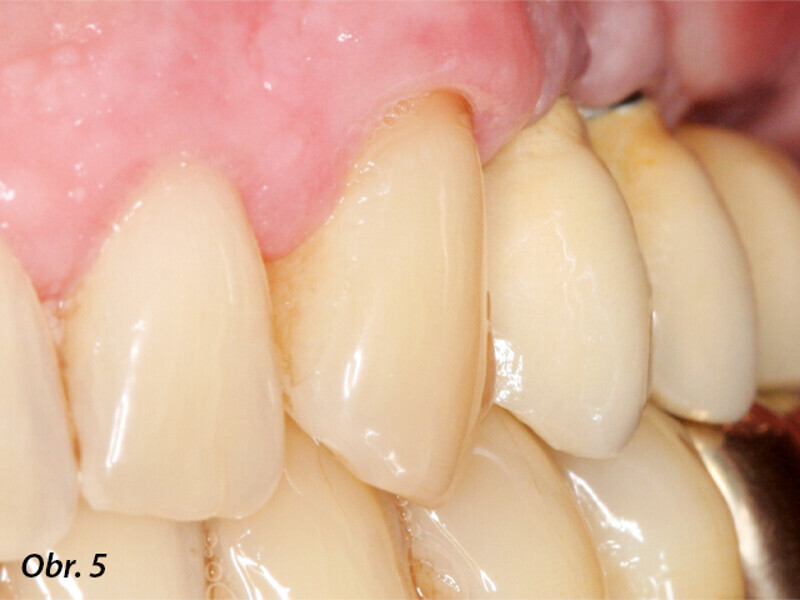

Rehabilitace unilaterální maxilární bezzubosti